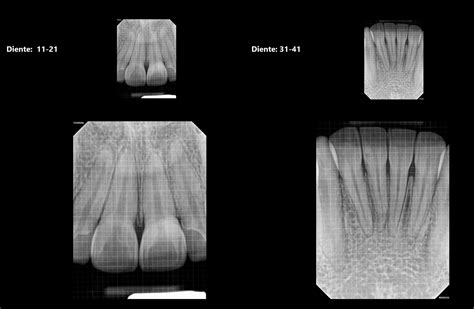

Las idóneas para la detección de caries son las radiografías periapicales o las de “aleta de mordida”. Son radiografías de pequeño tamaño y alta sensibilidad que nos muestran con gran detalle las coronas y raíces de los dientes. La ortopantomografía (radiografía de toda la boca) nos ayudará a determinar el nivel óseo general, presencia de terceros molares (muelas del juicio), lesiones en las raíces de los dientes (granulomas infecciosos), etc.

La desmineralización y destrucción de las capas del diente se observa como una imagen radiolúcida (zona negra alrededor/dentro del diente). En la consulta dental realizamos controles radiográficos periódicos. Se hacen cada 6, 9 o 12 meses, dependiendo del riesgo de caries del paciente, la presencia de múltiples reconstrucciones interproximales (interdentales), etc.

En la imagen de la izquierda se aprecia una caries debajo de un empaste antiguo. Es importante tener en cuenta que el diagnóstico temprano de las caries repercutirá en un mejor pronóstico del diente.

Ejemplo de caries detectada en una radiografía dental

En obturaciones antiguas (empastes/reconstrucciones) controlaremos que los márgenes de las restauraciones estén correctos, ya que en el material artificial no se producirán caries, pero en el tejido dental de alrededor sí podrían aparecer filtraciones. En la imagen que señala la flecha vemos una imagen radiolúcida (oscura) que indica la falta de material dental, la presencia de una zona “hueca”. Caries.